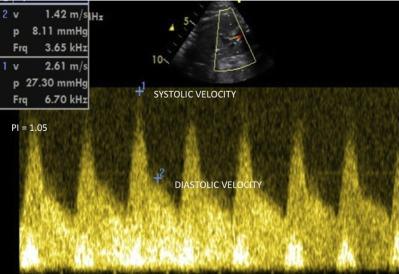

Fetal circulation has characteristic features, being morphologically and functionally different from extrauterine circulation. The ductus arteriosus plays a fundamental role in directing the blood flow to fetal inferior body parts. Basically, the ductus arteriosus directs 80-85% of the right ventricular output arising from the superior vena cava, coronary sinus, and a small part from the inferior vena cava to descending aorta. Its histological structure is made up predominantly by a thick muscular layer, differently from the aorta and the pulmonary artery, which increases with gestational age. The fibers have a circumferential orientation, especially at the external layers, facilitating and making effective ductal constriction. These factors may generate lumen alterations which may cause fetal and neonatal complications, such as heart failure, hydrops, neonatal pulmonary hypertension, and even death. Classically, maternal administration of indomethacin and/or other antiinflammatory drugs interfere in prostaglandins metabolism, causing ductal constriction. However, many cases of fetal ductal constriction, as well as of persistent neonatal pulmonary artery hypertension, remain without an established etiology, being referred as "idiopathic." In recent years, a growing body of evidence has shown that herbs, fruits, nuts, and a wide diversity of substances commonly used in daily diets have definitive effects upon the metabolic pathway of inflammation, with consequent inhibition of prostaglandins synthesis. This antiinflammatory action, especially of polyphenols, when ingested during the third trimester of pregnancy, may influence the dynamics of fetal ductus arteriosus flow. The goal of this review is to present these new observations and findings, which may influence dietary orientation during pregnancy.

胎儿循环具有独特的特征,在形态和功能上与宫外循环不同。动脉导管在引导血液流向胎儿身体下部起着重要作用。基本上,动脉导管将来自上腔静脉、冠状窦以及一小部分下腔静脉的右心室输出量的80%-85%导向降主动脉。其组织结构主要由一层厚厚的肌肉层组成,这与主动脉和肺动脉不同,且会随着孕周增加。纤维呈圆周方向排列,尤其是在外层,有助于并使导管有效收缩。这些因素可能导致管腔改变,进而引起胎儿和新生儿并发症,如心力衰竭、水肿、新生儿肺动脉高压,甚至死亡。传统上,孕妇使用吲哚美辛和/或其他抗炎药物会干扰前列腺素代谢,导致导管收缩。然而,许多胎儿导管收缩以及持续性新生儿肺动脉高压的病例仍病因不明,被称为“特发性”。近年来,越来越多的证据表明,草药、水果、坚果以及日常饮食中常用的多种物质对炎症代谢途径有确切影响,从而抑制前列腺素合成。这种抗炎作用,尤其是多酚类的抗炎作用,在妊娠晚期摄入时,可能会影响胎儿动脉导管的血流动力学。本综述的目的是介绍这些新的观察结果和发现,它们可能会影响孕期的饮食指导。